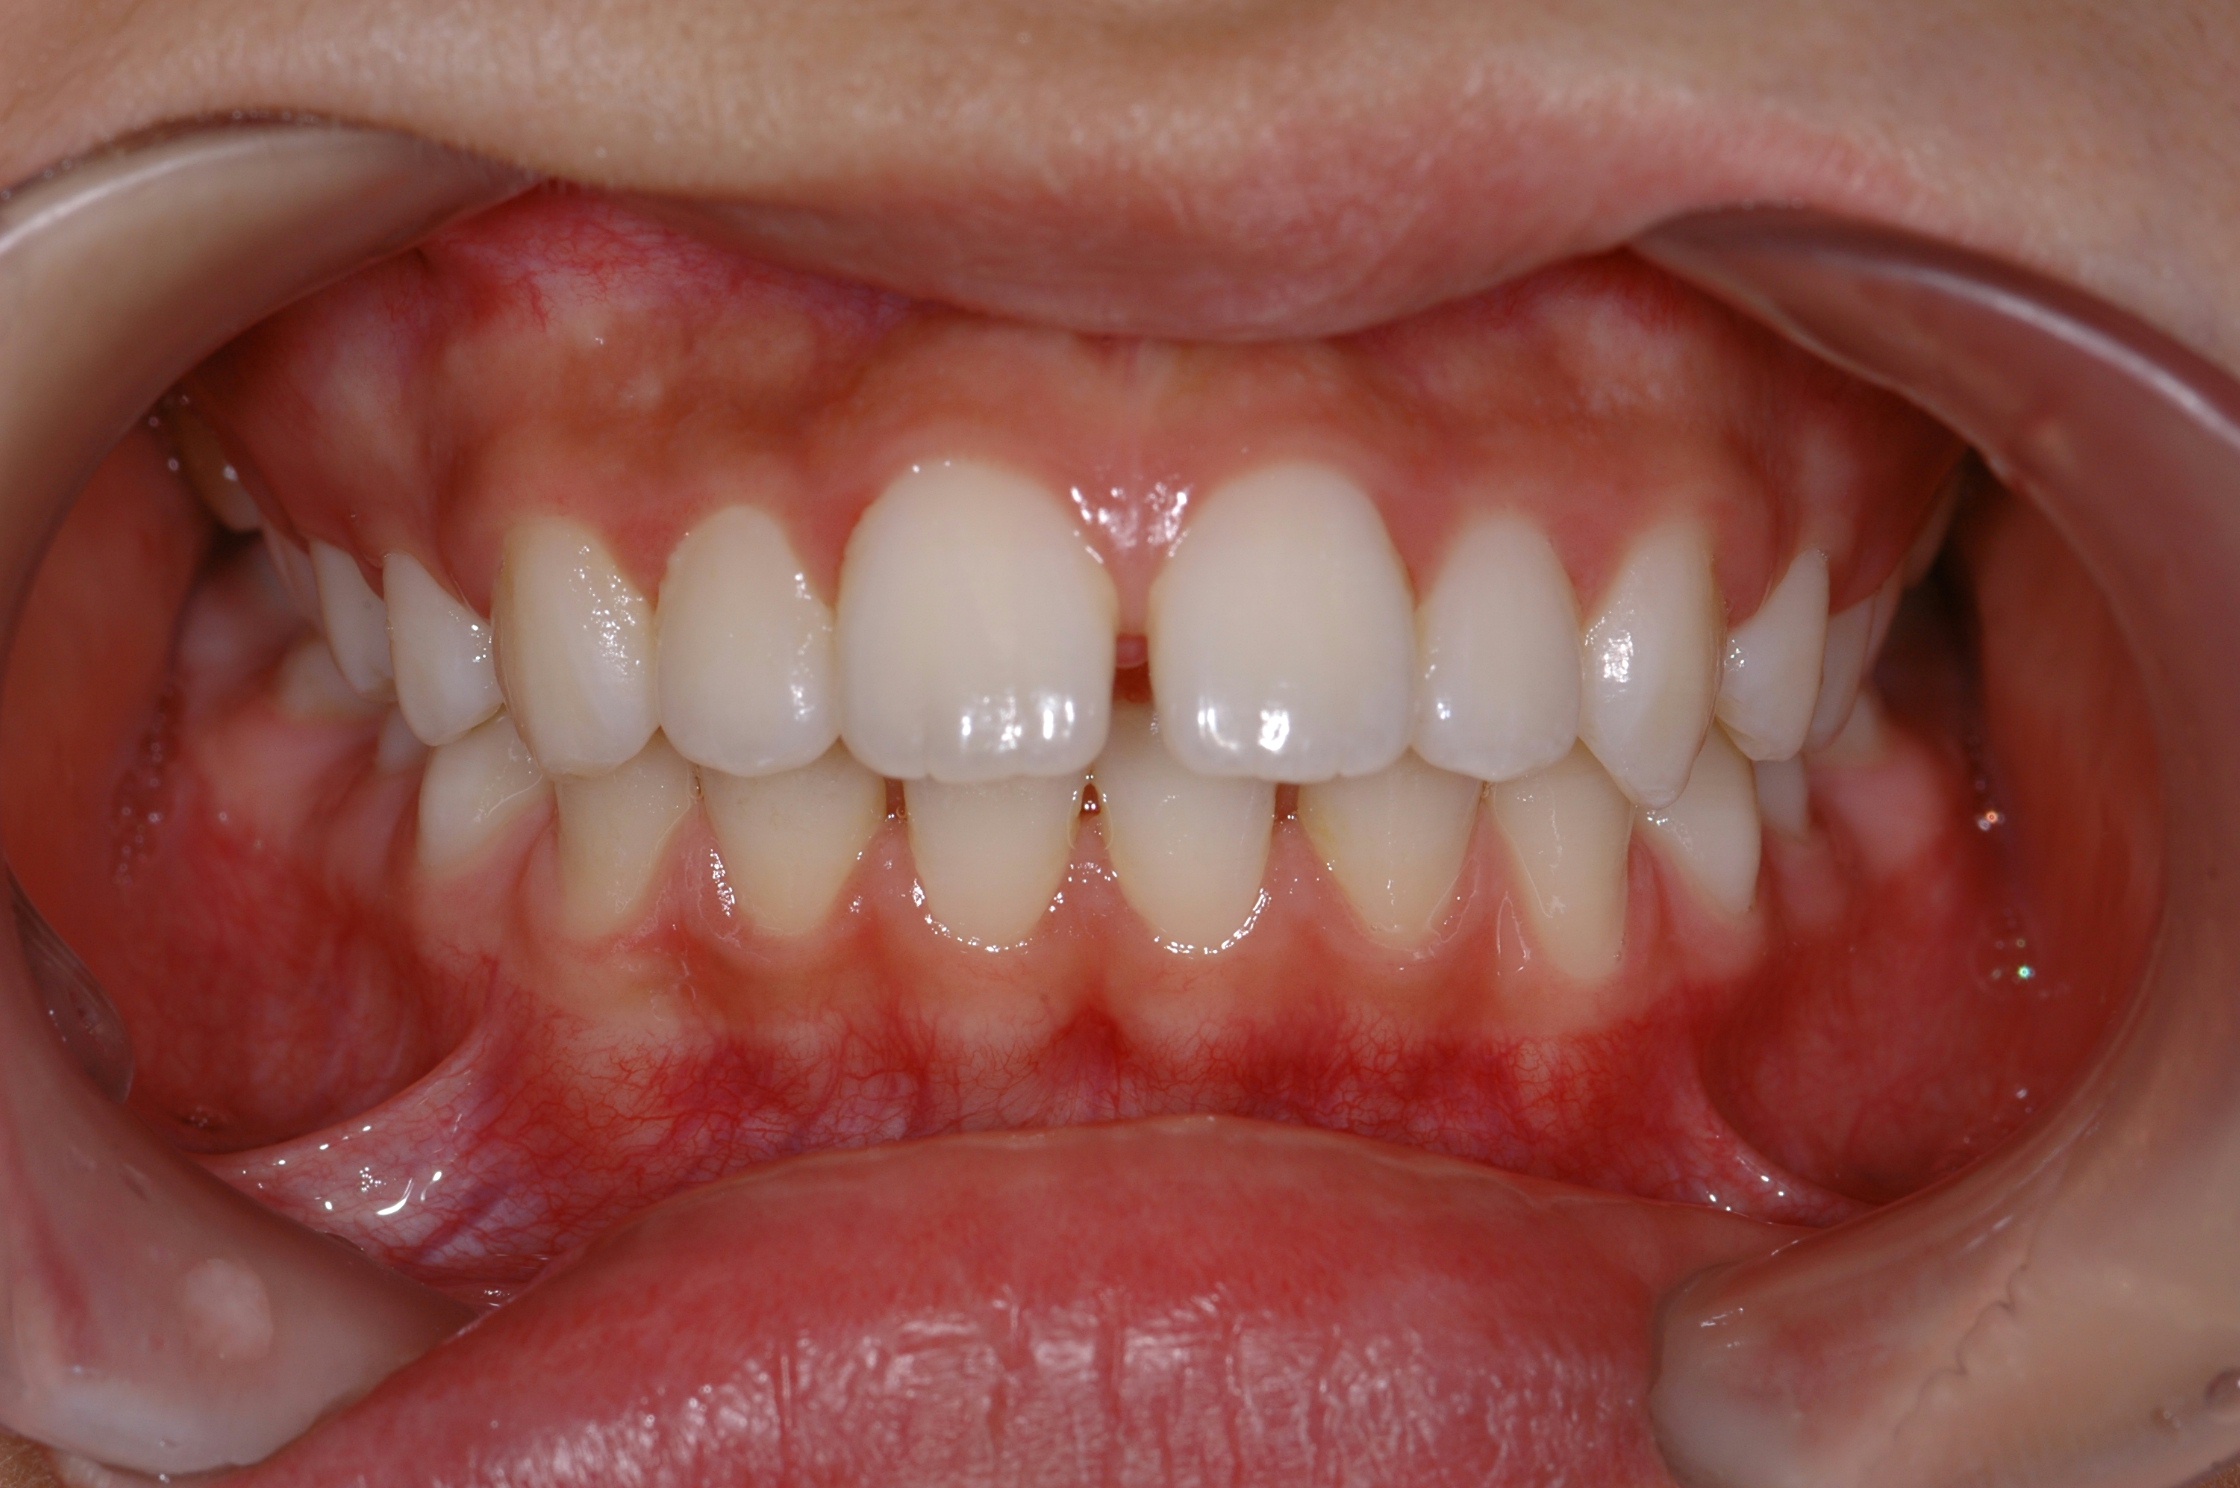

치료 후 사진입니다.